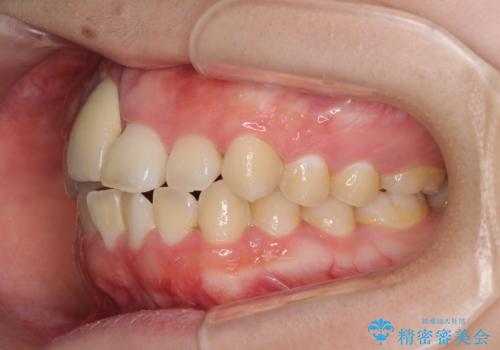

- 中学生の頃にぶつけた前歯に不格好なクラウンが装着されており、出っ歯な印象になっていることを気にして来院された患者様です。

ぶつけてしまった歯は保存が困難な状況であったので抜歯をし、ワイヤー矯正により歯列を整えつつ前歯の突出感を解消することとしました。